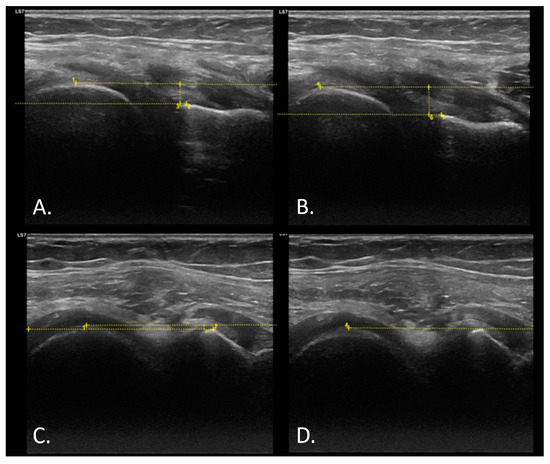

2.5.1. Anteroposterior Displacement of the Tibia Measured with Ultrasound

- Stoianov, A.G.; Pătrașcu, J.M.; Hogea, B.G.; Andor, B.; Mișcă, L.C.; Florescu, S.; Onofrei, R.R.; Pătrașcu, J.M. Dynamic Ultrasound Assessment of the Anterior Tibial Translation for Anterior Cruciate Ligament Tears Diagnostic. J. Clin. Med. 2022, 11, 2152. [Google Scholar] [CrossRef]